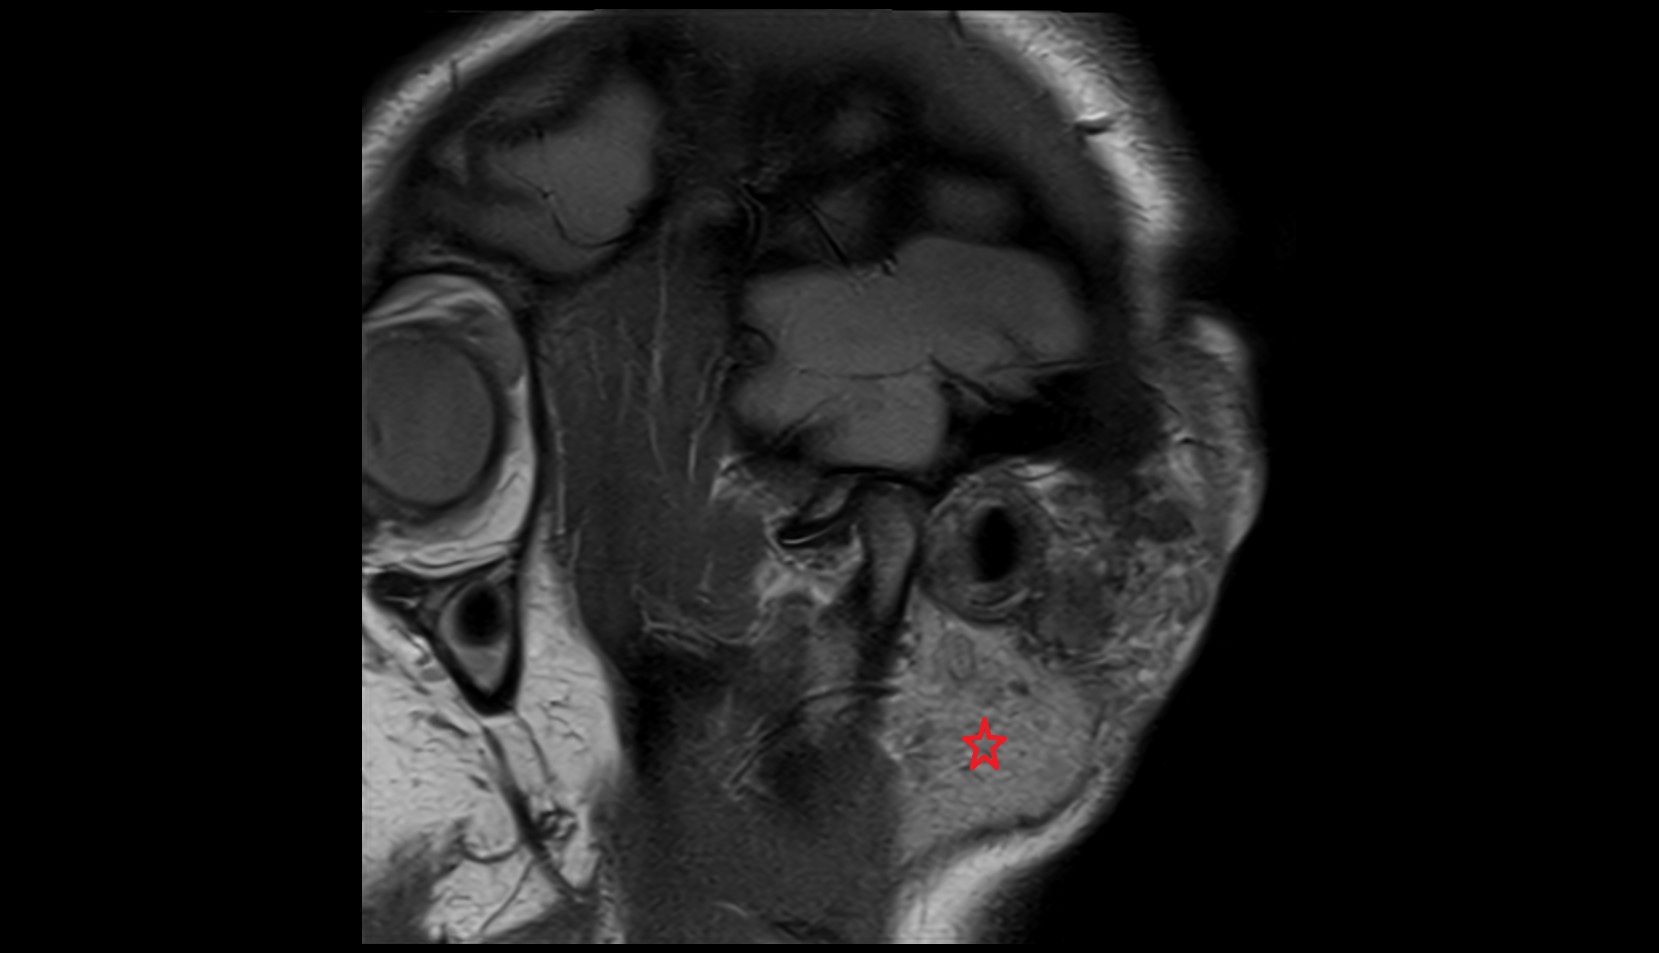

- Temporomandibular joint

- Mandibular condyle

- Mandibular fossa

- Articular disc of temporomandibular joint

- Articular eminence